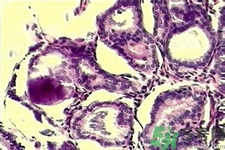

微鈣化作用是可能在迅速分解細(xì)胞的部位找到的鈣斑點(diǎn)。這些由迅速分解細(xì)胞留下的殘余物可以顯示為微鈣化作用。當(dāng)它們成群大量出現(xiàn)時(shí),即表示有小腫瘤的可能。

乳腺微鈣化作用

是可能在迅速分解細(xì)胞的部位找到的鈣斑點(diǎn)。這些由迅速分解細(xì)胞留下的殘余物可以顯示為微鈣化作用。當(dāng)它們成群大量出現(xiàn)時(shí),即表示有小腫瘤的可能。